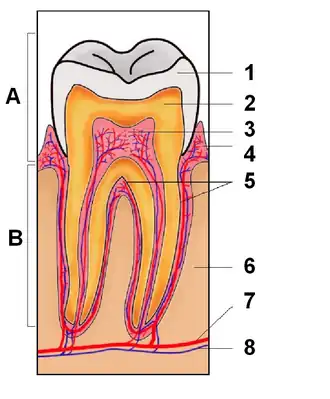

Dente é uma estrutura localizada na boca que é dura, saliente e esbranquiçada composta por polpa, dentina e esmalte que é originada no maxilar e na mandíbula (ou arcada dentária no ser humano) de muitos vertebrados.[1] É usado para cortar, prender e triturar alimentos, preparando-os para serem deglutidos.

Um humano adulto tem normalmente 32 dentes, dezesseis na mandíbula e dezesseis na maxilar. Os quatro incisivos, localizados à frente, cortam pedaços de comida não muito duros. Junto deles, estão os dois caninos, um de cada lado (sendo quatro no total). Por serem pontiagudos, servem para dilacerar e perfurar. Os incisivos e os caninos preparam uma quantidade de alimento para serem deglutidos. Os quatro pré-molares e os seis molares cumprem as funções de o cortar, esmagar e triturar.

Os dentes se unem ao osso alveolar (alvéolo de sustentação), por meio do ligamento periodontal, em uma articulação denominada Gonfose. As articulações fibrosas, como as gonfoses, caracterizam-se por unir os ossos através de tecido conjuntivo fibroso, permitindo pouco ou nenhum movimento.

Taurodontia